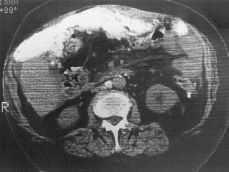

La radiografía simple de abdomen muestra múltiples áreas calcificadas distribuidas difusamente (Fig. 1). Se realiza TC abdominal donde se define una masa pélvica, heterogénea, parcialmente calcificada, con bordes mal definidos, sugestiva de neoplasia ginecológica. También se observa engrosamiento mesentérico y de épiplon mayor, parcialmente calcificado (Fig. 2), calcificaciones perihepáticas, periesplénicas y ascitis, (Fig. 3). Hallazgos sugestivos de carcinomatosis peritoneal abundantemente calcificada.

Figura 1. Radiografía simple de abdomen con extensas áreas de calcificación diseminadas por la cavidad abdominal, de distribución intraperitoneal